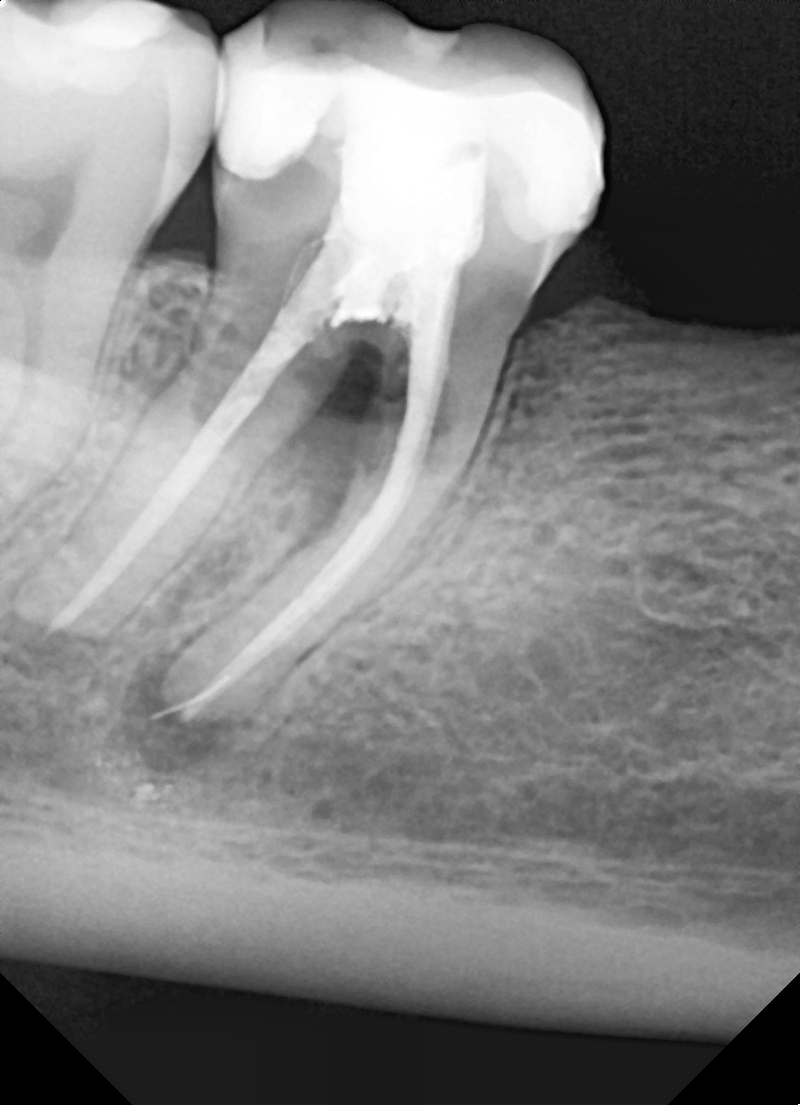

Ryc. 1a. Zmiany zapalne furkacji zęba 47.  Ryc. 1b. Rtg 7 dni po augmentacji.

Wszystkie zabiegi przeprowadzono w znieczuleniu miejscowym 4% Artykainą z dodatkiem Noradrenaliny. W pierwszym etapie usunięto ząb 47. Stwierdzono częściowe uszkodzenia blaszki korowej przedsionkowej. Po opracowaniu rany ubytek wypełniono cementem regeneracyjnym (1 cm3) (ryc. 5).

Ryc. 5. RTg 7 dni po usunięciu 47 i augmentacji zębodołu